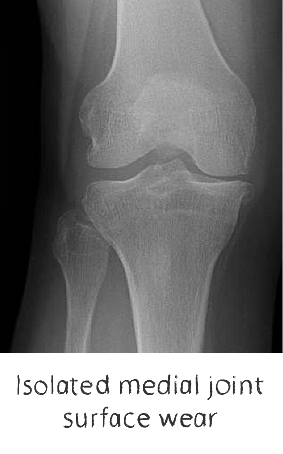

Plain film x-rays are taken to assess the joint

These are usually taken prior to your appointment. These help to confirm the diagnosis, assess the wear pattern and look for particular deformities. They can show old metalware and its position in the bone.

If the knee joint is arthritic in only one of the 3 parts of the knee joint, partial knee replacement is possible, rather than replacing the whole joint.